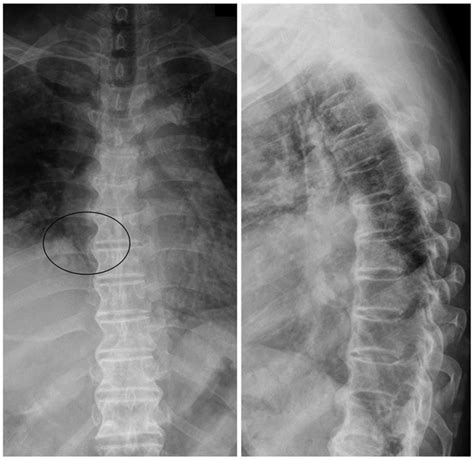

Spinal tumors are abnormal growths of cells within or surrounding the spinal cord or the spinal column. These growths can be malignant (cancerous) or benign, but even non-cancerous tumors can cause severe health complications by compressing the spinal cord or nerves. When the tumor is malignant, it requires immediate professional evaluation by an oncologist or a spine specialist to determine the appropriate course of action.

The spine is a complex structure that serves as the main support for the body and protects the delicate spinal cord. When a tumor develops, it interferes with these functions, leading to a variety of neurological and physical symptoms. The location and growth rate of the tumor dictate the specific signs a patient might experience.

To determine if these symptoms are linked to spinal malignancy, doctors utilize various diagnostic tools. Because the first symptoms of spinal cancer are often non-specific, clinical history is paramount. A physician will usually perform a physical examination followed by imaging studies to visualize the spinal structure.

MRI Scan Provides highly detailed images of the spinal cord, nerves, and surrounding soft tissues.

CT Scan Excellent for evaluating the bone structure of the vertebrae.